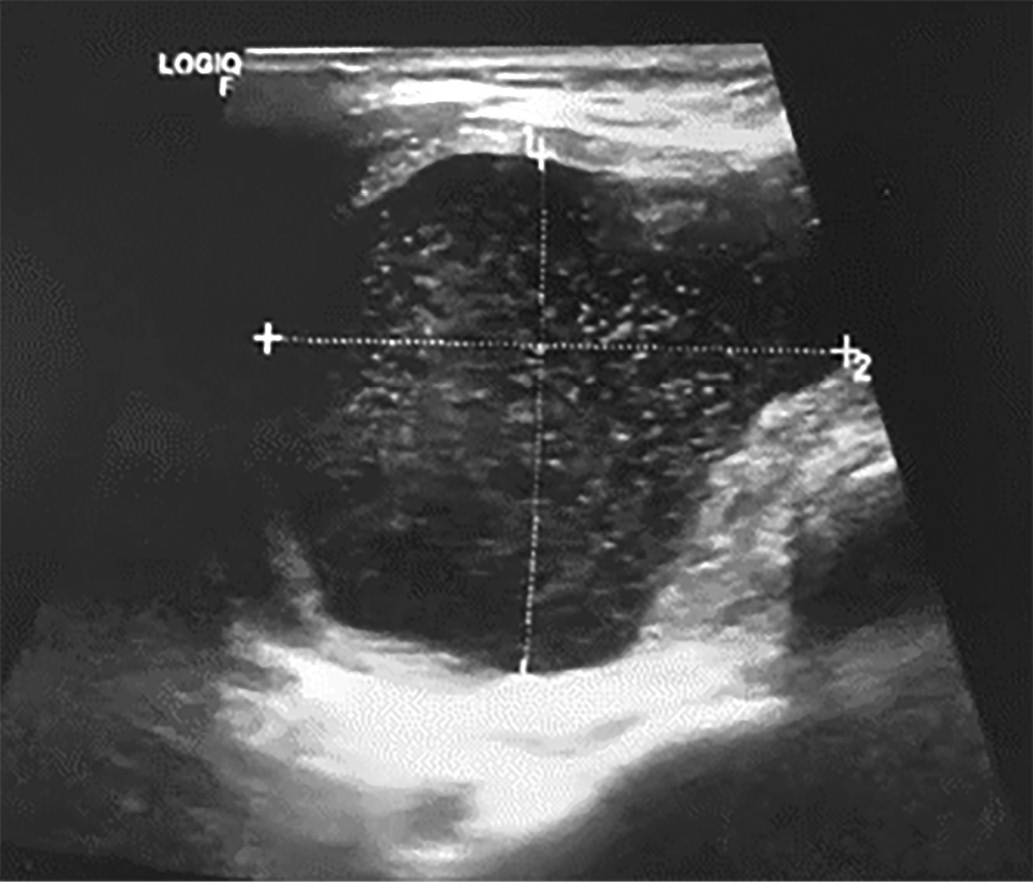

2. Рисунок 2. Кистозный компонент узла правой доли щитовидной железы.

Тема

Тип Исследовательские инструменты

Посмотреть (131KB)